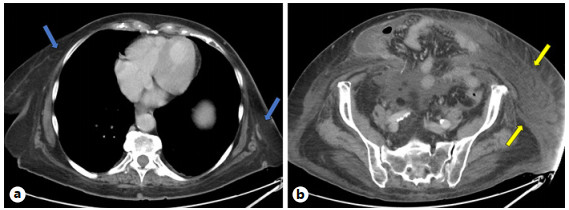

Abstract: Small bowel-origin carcinoid tumor is indolent but may metastasize relentlessly to various sites, including the liver. Over the past 9 years, we have treated a 69-year-old woman who has undergone 5 percutaneous liver ablations, 5 hepatic intra-arterial chemoembolizations, an ovarian cryoablation, and a trans-ventral hernia mesenteric cryoablation. These interventions are all related to her inoperable carcinoid malignancy. After the patient presented with swelling of the abdomen and both lower extremities, computed tomography (CT) angiography was performed, revealing a circumferential hepatic metastatic mass encasing the intrahepatic inferior vena cava (IVC) and extensive third spacing of fluids specific to the IVC distribution below the diaphragm. A venogram of the intrahepatic IVC revealed extrinsic compression causing 95% narrowing of the vessel. A balloon was advanced to the level of the lesion and inflated, increasing the caliber of the vessel. Subsequently, 2 covered aortic stent graft cuffs were deployed in an overlapping fashion within the lumen of the IVC, traversing the area of narrowing. Next, an open-cell aortic dissection stent was placed across both overlapping aortic stents from the renal veins to the hepatic veins. Following this, three 17-gauge cryoablation probes were inserted into the segment 1 intrahepatic lesions encasing the newly stented IVC via an anterior percutaneous approach. Two 10-min freeze cycles were performed with intraoperative CT imaging, demonstrating circumferential coverage of the lesions. Posttreatment venogram revealed patent stent grafts within the intrahepatic IVC, and restoration of vessel patency. No immediate postoperative complications were noted. The patient’s abdominal and lower extremity swelling resolved completely within 1 week after procedure. Two-month follow-up CT demonstrated markedly decreased size of the metastatic lesions and no adverse effects. Six- and 9-month PET-CT scans demonstrated maintained patency of the IVC stent. This palliative procedure allowed the patient to maintain good performance status and alleviated her symptoms of IVC syndrome. The radial force generated by the multiple aortic stents will ostensibly maintain the patency of the intrahepatic IVC. Cryoablation of the encasing metastatic lesion was performed with markedly decreased size of the tumor on the 2-month follow-up.